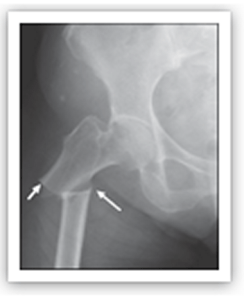

La notificación de fracturas atípicas de fémur en pacientes que tomaban bifosfonatos ha ido aumentado desde los casos únicos

iniciales, hasta el punto que a mayo de 2011se han comunicado 329 casos. Este tipo de fracturas se presentan con una frecuencia muy baja en pacientes que usan bisfosfonatos, se les estima una incidencia de 1 por 1000, calcualndose que por cada 100 fracturas femorales que previenen el tratamiento con bifosfonatos, se produciría 1 fractura atípica de fémur. Se caracterizan en la clínica por ser fracturas que se producen con traumatismos leves o inexistentes y ser precedidos por dolor en la pierna, en la mitad del muslo, y radiológicamente por ser fractura subtrocántereas, transversales y con aumento de la cortical cerca del sitio de la fractura..

Es difícil de probar que los bifosfonatos causen las fracturas atípicas, pero los estudios epidemiológicos publicados hasta la fecha con confirmación radiográfica de la fractura atípica sugieren una relación causal entre el uso de bisfosfonatos (todos, ya que parece haber efecto de clase) y la aparición de la fractura, que se incrementaría con la duración del tratamiento.